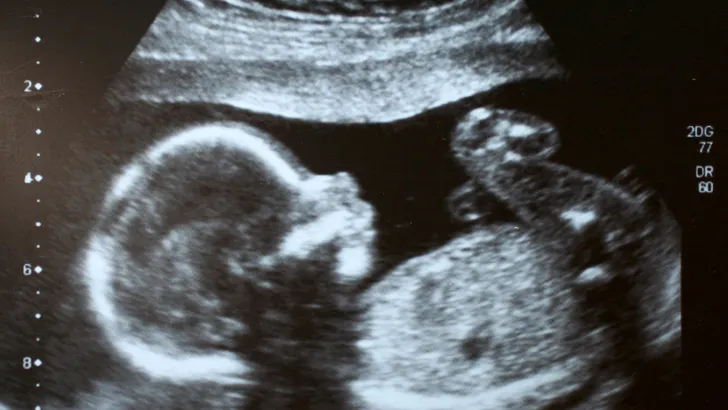

“Een kleine handeling kan al veel betekenen. Vraag niet of iemand de echo wil meenemen na een slecht nieuws gesprek — geef hem gewoon mee. Zo’n tastbaar aandenken kan jaren later van grote waarde blijken. Veel vrouwen bewaren die echofoto in een doosje met herinneringen. Dat helpt bij het integreren van het verlies in hun leven. En als je dit leest en denkt: ‘‘Ik heb die echo nooit meegekregen’’ ‒ ziekenhuizen en abortusklinieken zijn verplicht zulke beelden jarenlang te bewaren. Je kunt ze meestal nog opvragen.”